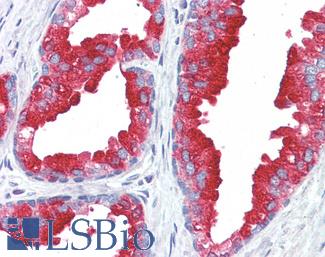

ERBB2 / HER2

Anti-ERBB2 / HER2 antibody IHC of human breast, carcinoma. Immunohistochemistry of formalin-fixed, paraffin-embedded tissue after heat-induced antigen retrieval. Antibody LS-B2133 concentration 5 ug/ml.